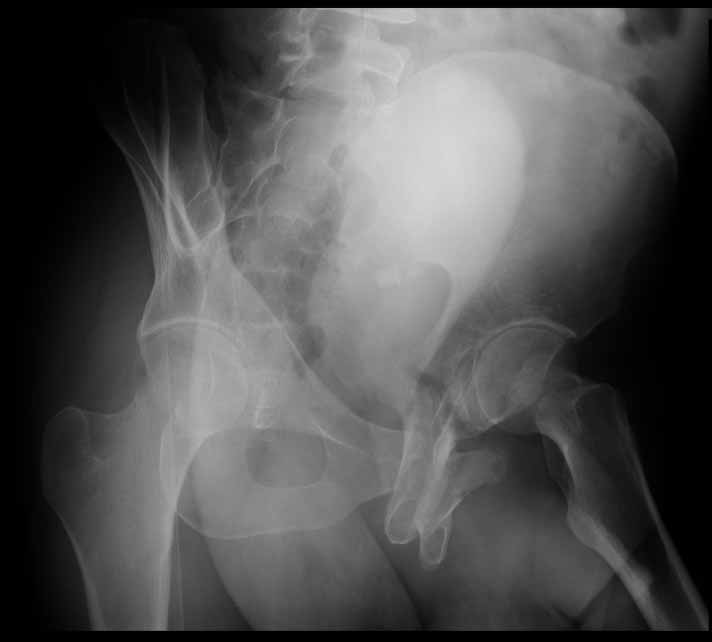

25 yo brittle diabetic, became hypoglycemic and passed out on his motorcycle. Sustained bilateral lateral Hoffa fractures with associated LCL injury on the right and right distal radius fracture. I have questions regarding his pelvic ring/acetabular fracture on the left. Appears to be a very low posterior column fracture with associated posterior wall, marginal impaction. Superior and inferior rami fractures as well on the left giving him a floating segment of inf ramus/ischium/posterior column, but no detectable posterior ring injury. Should the posterior column/posterior wall fracture be addressed surgically because of the marginal impaction? Or is this fracture low enough to be treated non-operatively? I appreciate the input.

It's an interesting case. The plain films show the impaction, but most of the joint looks pretty good. The CT cuts look awful, though.

The impaction is so big I don't think I would ignore it. It IS down low, but it takes up almost the whole southern hemisphere of his joint.